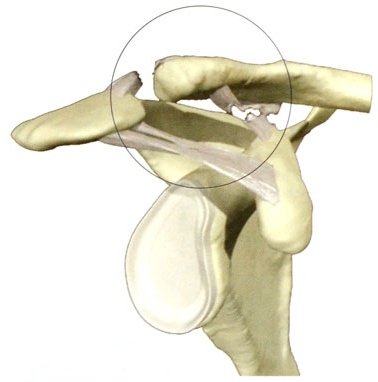

Звичайно ж, оскільки зв'язок, що прикріплюються до ключиці кілька, то можливі різні варіанти їх розривів. Наприклад, може розірватися тільки капсула акроміально-ключичного суглоба - в такому випадку вивиху не відбудеться або буде підвивих, оскільки ключицю будуть тримати інші зв'язки. Якщо розірвуться інші зв'язки (конічна і трапецієвидна зв'язки), відбудеться вже вивих ключиці.

Вивих акроміального кінця ключиці: зліва - неповний (підвивих), клювовидно-ключично зв'язка ціла; праворуч - повний, порвані конічна і трапецієвидна зв'язки, які утворюють єдину клювовидно-ключичну зв'язку.